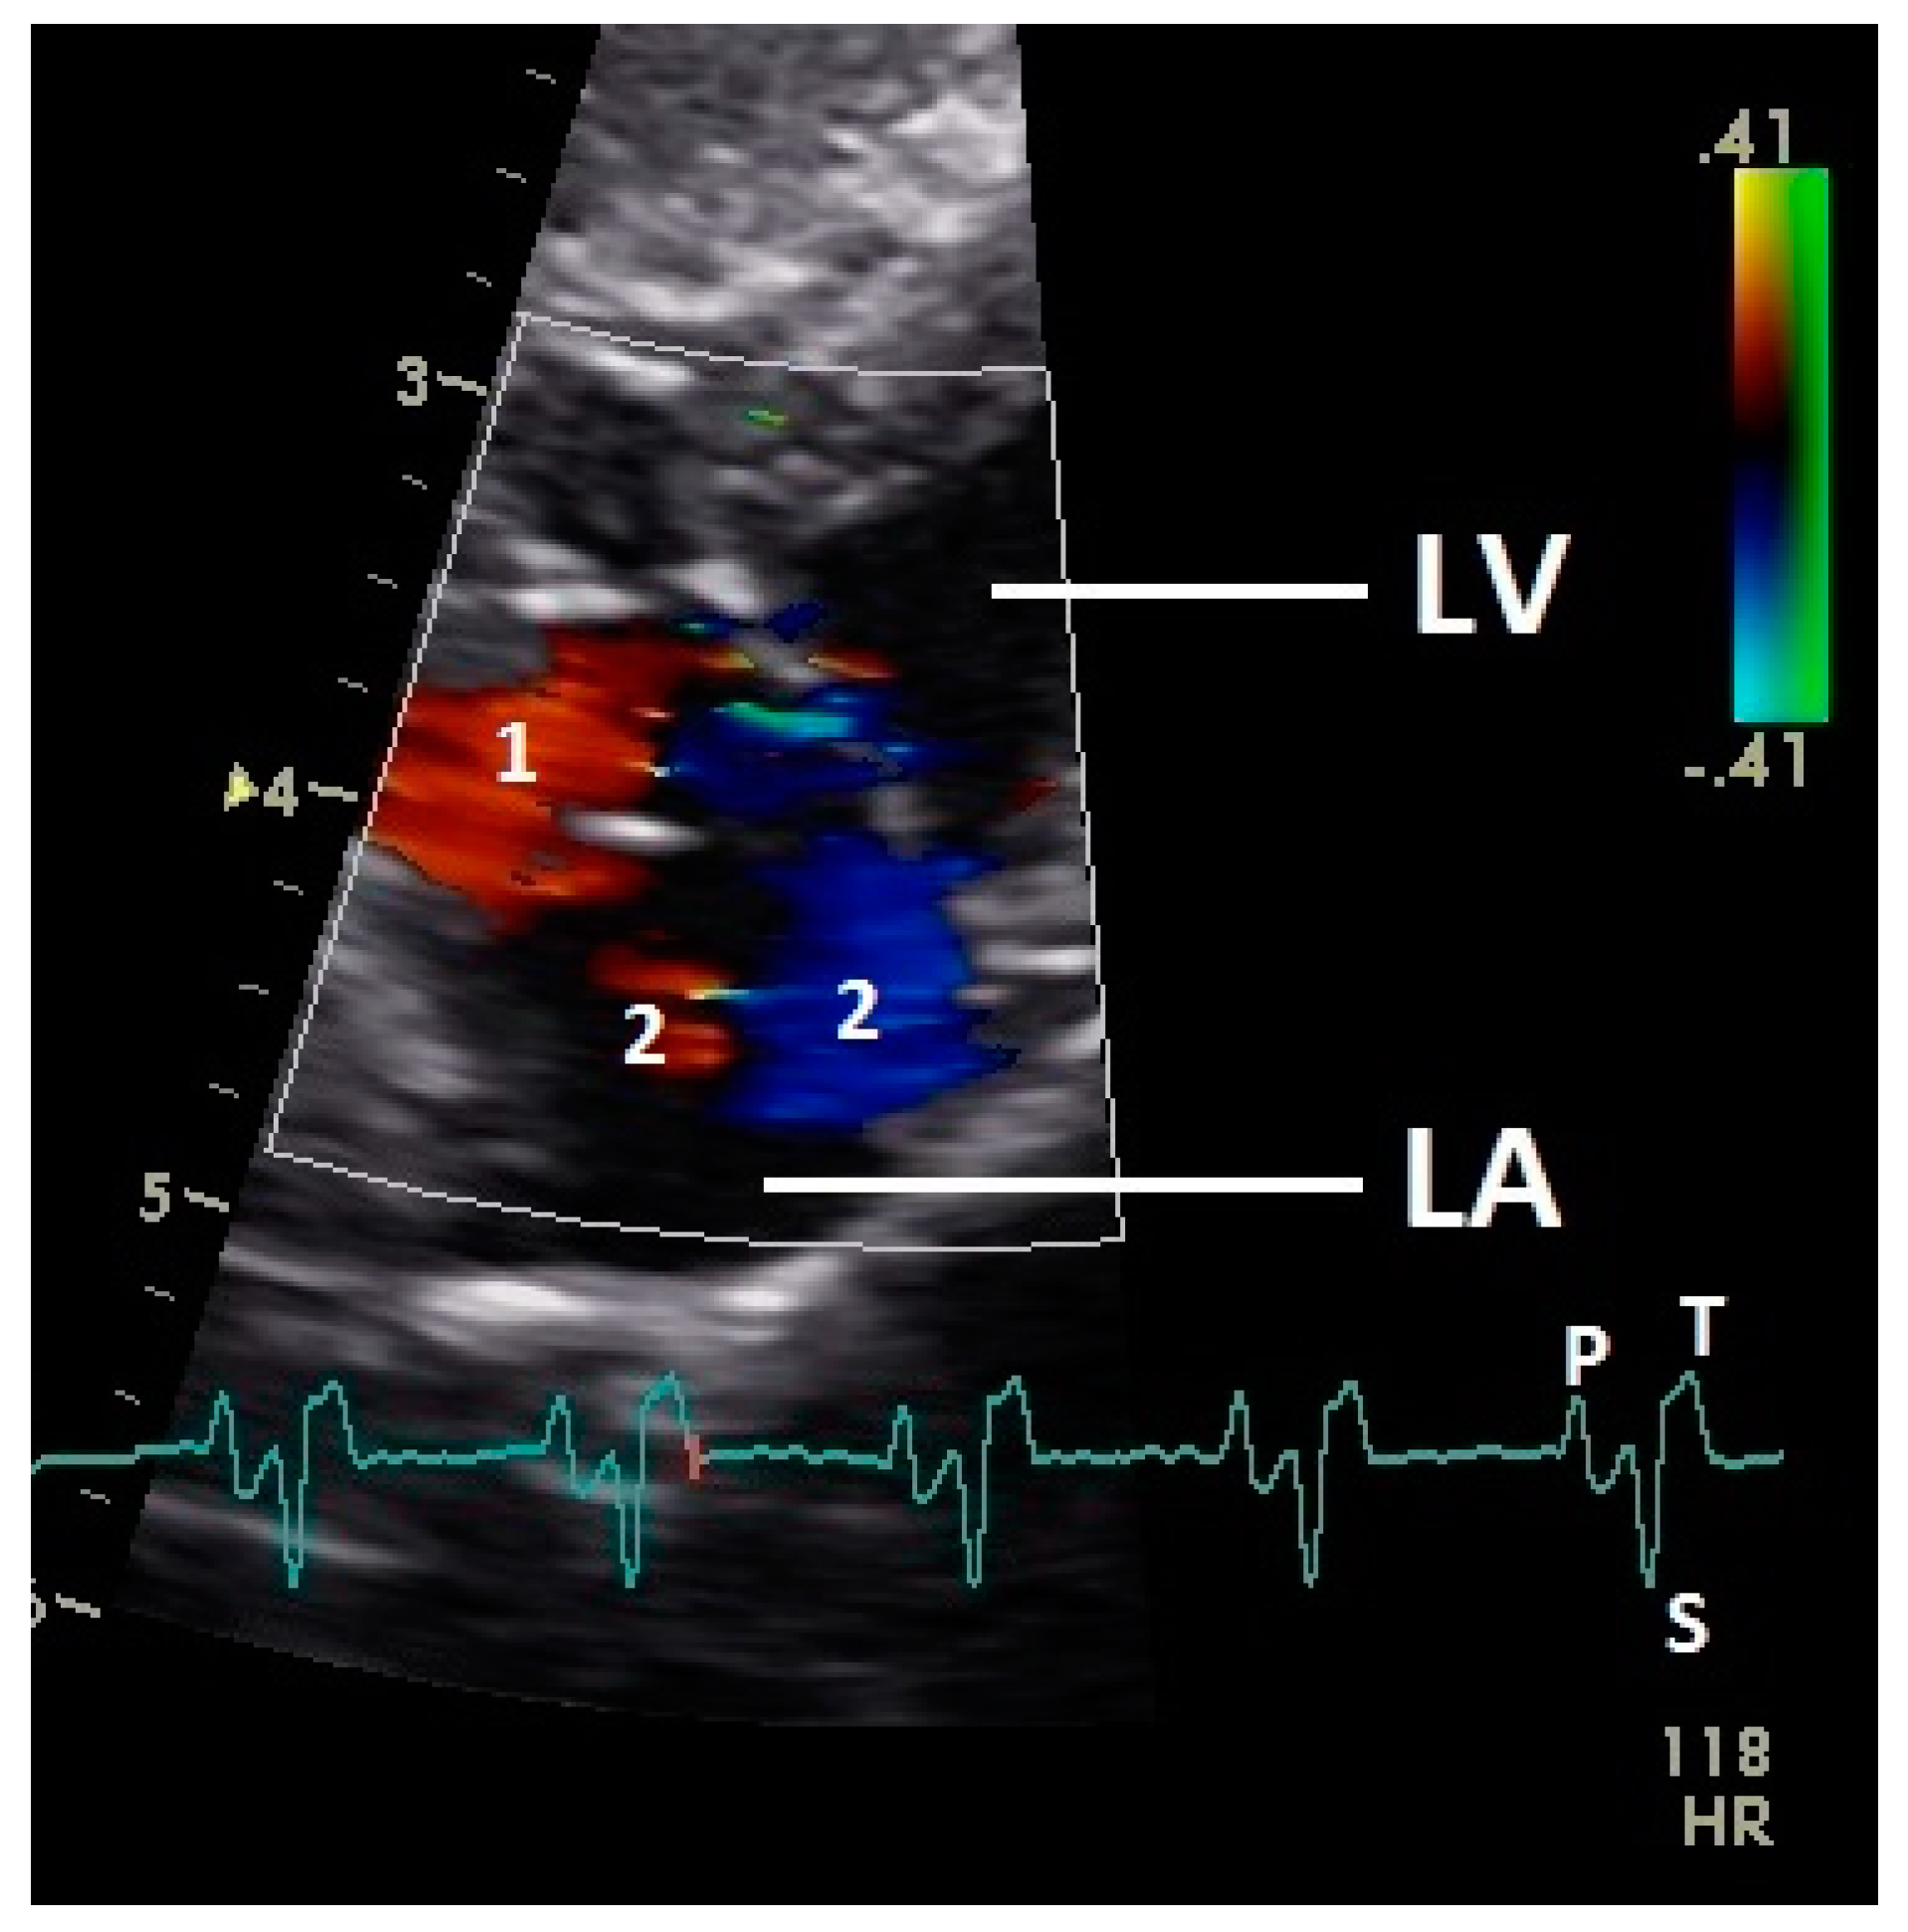

Figure 6.

Color Doppler image of the late blood inflow in the left atrium (red signal; 1) and blood flow vortex formation (2). LV: left ventricle; LA: left atrium; HR: heart rate. Electrocardiogram: P: P wave, S: S wave, T: T wave. The color scale on the right of the image is calibrated in m s−1.

Constant simultaneous occurrences of red and blue color in the Doppler images of ventricles and atria show the presence of typical constant blood flow vortex formations in the avian heart, comparable to the mammalian heart [32]. Vortices in the cardiovascular system are supposed to play fundamental roles in normal physiology and provide a proper balance between blood motion and the stresses on the surrounding tissues [32]. In the color Doppler examinations of the pigeon heart in the “four-chamber view”, a vortex clockwise in the left atrium and counter-clockwise in the right atrium were observed. In this context the valva pulmonis of the left atrium is discussed as an important anatomical structure for sealing the atrial cavum [1]. However, the color Doppler images in our investigation show that in diastole (atrial contraction) and systole (atrial filling) the position of the valva pulmonis is very constant. There is no evidence for a motion of this valve which could contribute to the closure of the left atrium (see Figure 5, Figure 6 and Figure 7). The main function of this anatomical structure seems to be to direct blood flow towards the left ventricle (see Figure 6). The passive filling of the atria was visible after the P wave of the ECG as a cause of the relaxation of the myocardium and in the time of the end of the T wave of the ECG as a cause of the ventricular pump mechanism by the myocardial contraction in the systole. The findings in the color Doppler sonographic examination of the ventricles allow the conclusion of the presence of an asymmetric vortex ring in the left ventricle in the passive and active ventricular filling with a stronger vortex behind the longer septal part of the left AV valve (see Figure 1, Figure 2 and Figure 3). It is possible that an asymmetric valve shape allows a typical vortex formation (larger vortex in the direction of the outflow tract) that enables a faster blood flow and emptying of the ventricle [33]. Similar vortex formations in the left ventricle are described in the mammalian heart [32,33]. In the right ventricle the active ventricular filling leads to a great counter-clockwise blood vortex in this ventricle. The blood flow behind the right AV valve in the active ventricular filling as well as the active movement of this muscular valve during the closure seem to be important for the development of this blood flow vortex (see Figure 8). In connection with the asymmetrical shape of the right ventricle and oblique arrangement of the right AV valve [1], the shape of the blood vortex simplifies the outflow of blood through the pulmonary artery.